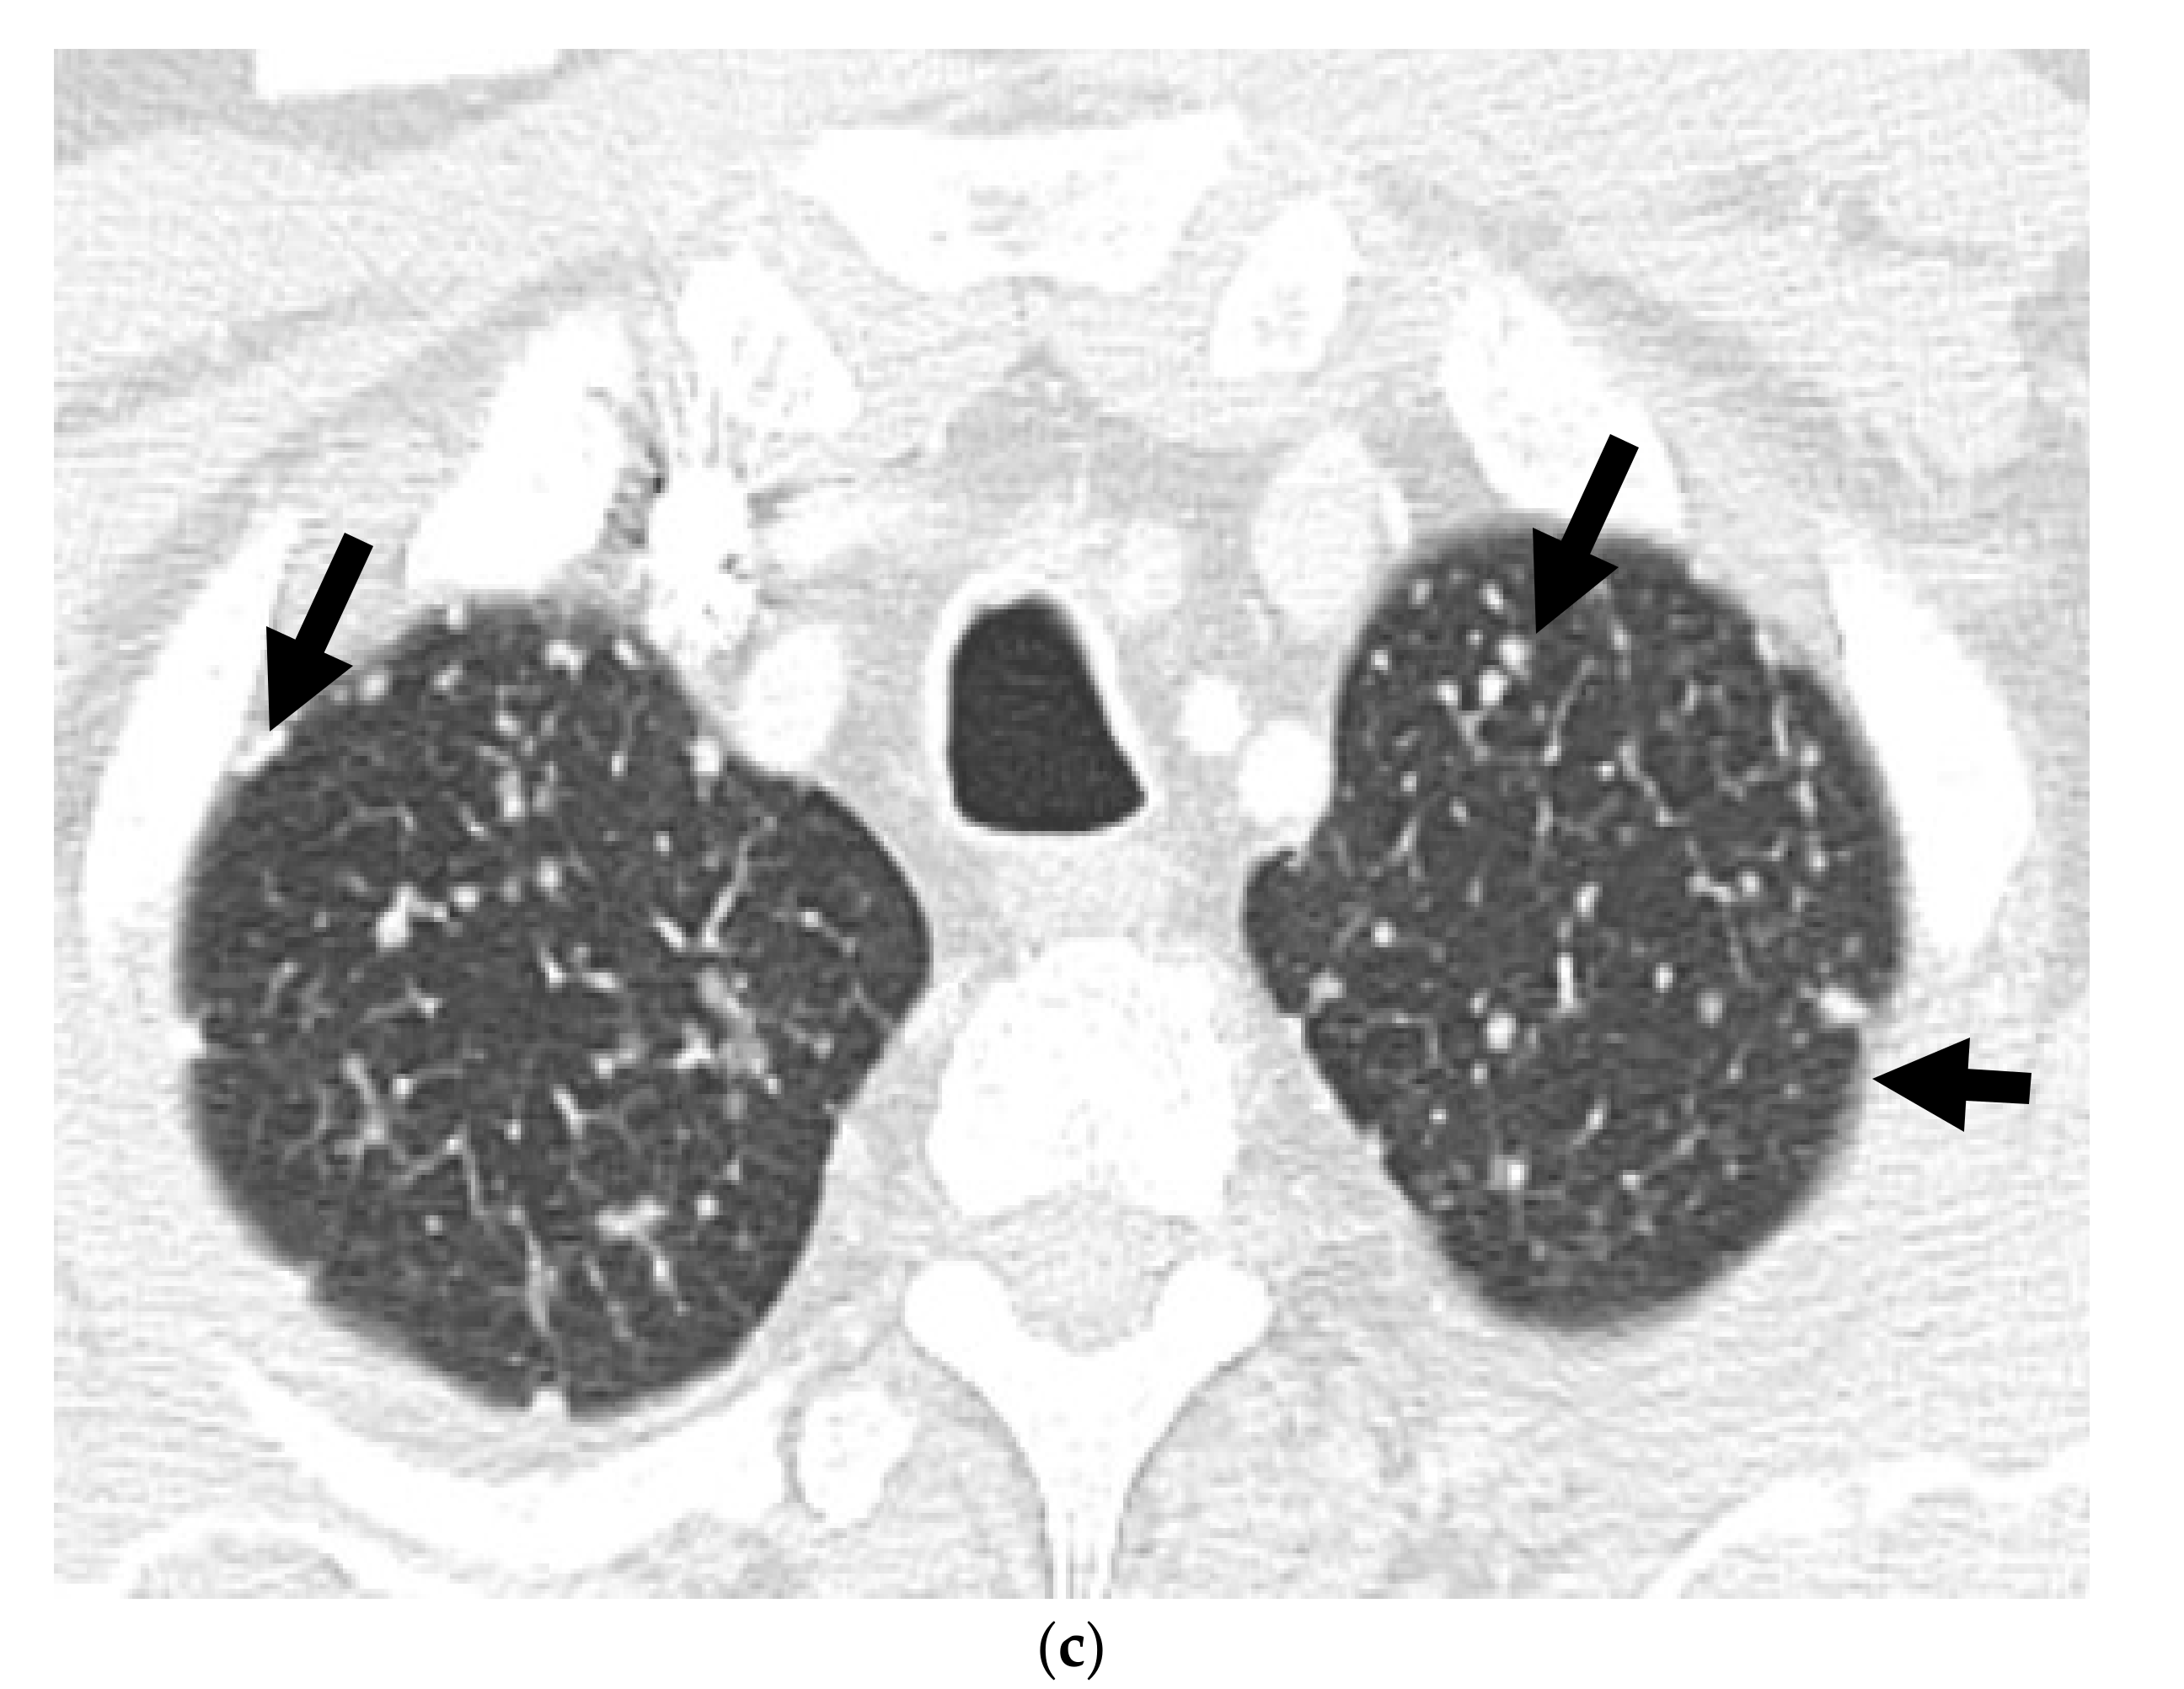

2.3.1. 18 F- Fluorodeoxyglucose (FDG)

- Spratt, D.E.; Gavane, S.; Tarlinton, L.; Fareedy, S.B.; Doran, M.G.; Zelefsky, M.J.; Osborne, J.R. Utility of FDG-PET in clinical neuroendocrine prostate cancer. Prostate 2014, 74, 1153–1159. [Google Scholar] [CrossRef] [PubMed]

- Shen, K.; Liu, B.; Zhou, X.; Ji, Y.; Chen, L.; Wang, Q.; Xue, W. The Evolving Role of 18F-FDG PET/CT in Diagnosis and Prognosis Prediction in Progressive Prostate Cancer. Front. Oncol. 2021, 11, 683793. [Google Scholar] [CrossRef] [PubMed]